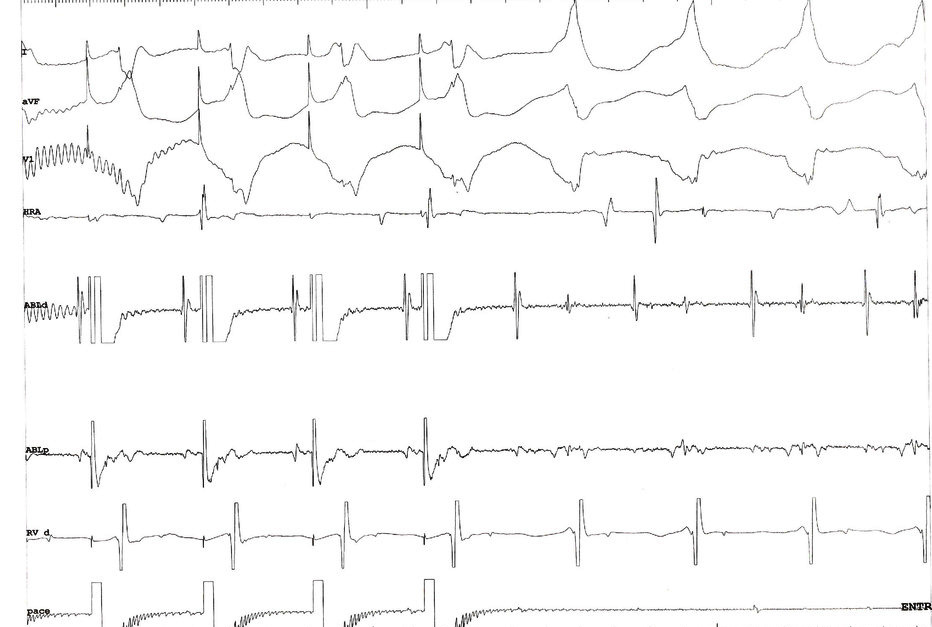

Double potentials = pace to identify

entrain_rv.jpg